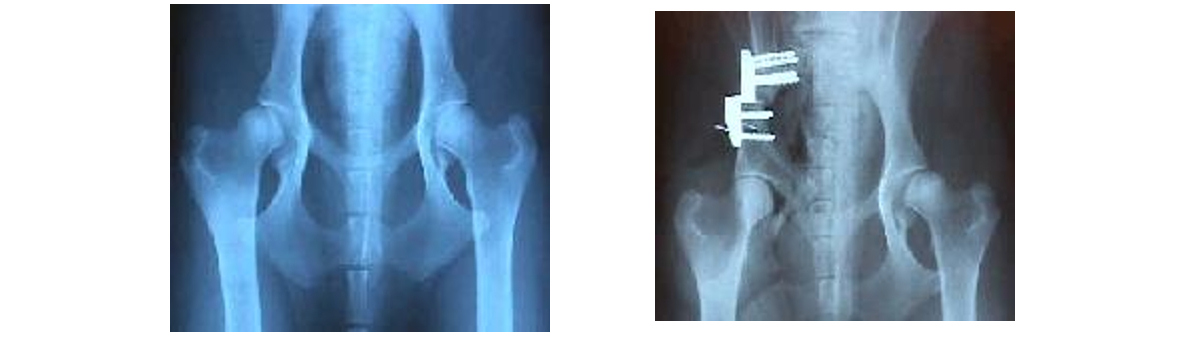

OSTEOTOMIA TRIPLA A osteotomia tripla do púbis, ísquion e ilíon,

liberta a parte acetabular, de forma a que se pode reorientar,

conseguindo uma maior congruência da mesma com a cabeça femoral,

diminuindo assim, a laxidão da cápsula articular, e evitarmos as

lesões degenerativas da articulação. O candidato ideal para uma

osteotomia tripla é um animal com displasia acetabular de 7 a 12

meses de idade com laxidão articular que clinicamente manifeste

sintomatologia e que não apresente sinais de degeneração

articular. Podemos rodar o acetábulo 20, 30 ou 40º.

O Hospital Veterinário do Porto com uma equipa cirúrgica

chefiada pelo Dr. Mário Santos, tem vindo ao longo de 4 anos, a

realizar as osteotomias triplas em muitos animais afetados, por

esta doença de todas as regiões do país. Cremos que é o melhor

método cirúrgico para corrigir a displasia, sendo a seleção dos

pacientes, assim como, a idade, de primordial importância para

que o êxito seja de 100%.

A rotação no caso acima descrito foi de 30 º, a radiografia foi efetuada após a cirurgia. Podemos verificar a introdução total da cabeça femoral no acetábulo no pós-cirúrgico. DARTROPLASTIA. É a cirurgia mais recente que utilizamos para corrigir a displasia em animais que já passaram os 12 meses de idade e que já não podem realizar uma osteotomia tripla. Contudo não são candidatos a uma cirurgia de prótese da anca ou muito menos a uma artroplastia por excisão. A cirurgia consiste em aumentar o acetábulo com uma técnica bastante eficaz e que mantém a cabeça do fémur estabilizada. Temos vindo a realizar esta técnica, desde há dois anos, conseguindo resultados extraordinários.